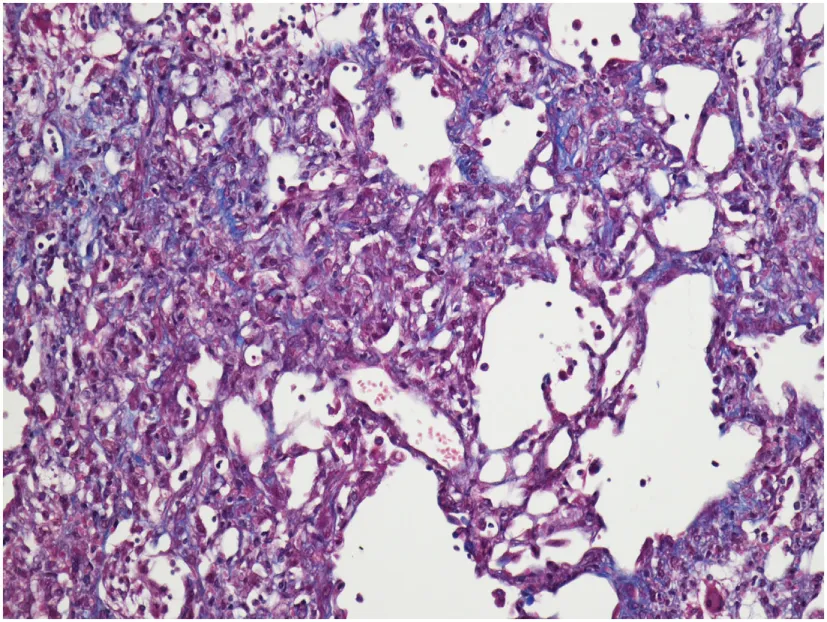

A study on Westies (109) found that the majority of dogs with IPF showed multifocal areas of accentuated subpleural and peribronchiolar fibrosis with occasional “honeycombing” and profound alveolar epithelial changes, reminiscent of human UIP and not commonly seen in NSIP. Interstitial fibroblastic foci, characteristic of UIP, were not seen in WHWTs with IPF. Progressive fibrosis, with intra-alveolar organizing fibrosis alongside interstitial mature collagen deposition, was present within the more severely affected areas of lung in WHWTs with IPF. Severe pulmonary lesions were seen more commonly in the caudal than in the cranial lung lobes.

The authors acknowledge the Lester and Sue Smith Foundation, Coalition for Pulmonary Fibrosis, and the Pulmonary Fibrosis Foundation for their support. The authors also acknowledge Amy Miele, BVM&S MRCVS (University of Edinburgh) for her contributions in providing veterinary histopathology images used in the construction of Table 1. AT is a recipient of a Marie Curie/Sklodowska ERS/RESPIRE 2 fellowship (8860-2015). All authors have no financial affiliations or conflicts of interest to disclose.